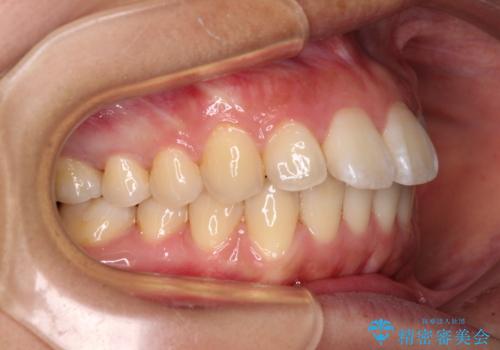

前に出ている前歯を引っ込めたい インビザライン矯正

- 前方に傾斜した上下の前歯を気にして来院された患者様です。

唇の閉じにくさや横顔のシルエットが気になるような突出感ではなかったため、インビザラインを用いて、歯列の遠心移動とIPR(歯と歯の間を削る)により前歯の傾斜を改善していくこととしました。

スムーズに終了すると思われましたが、インビザライン矯正独特の奥歯が咬み合わない状態が続き、更には遠方へ転居されたこともあり、治療期間は長引いてしまいました。